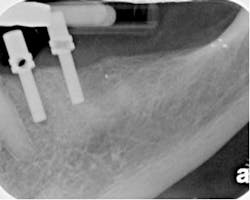

Clinical case (#28-29) treated with the Twisted File* and RealSeal* master cones trimmed for tugback as described in the article.One of the issues raised is clinical and the other is related to commercial interest. With regard to commercial interest, I am on the advisory board of SybronEndo and receive an honorarium for some aspects of that work, for example lectures. I am not incentivized to sell Twisted Files (TF) or receive a royalty for TF sales. I use TF because in my hands it is the finest rotary nickel titanium (RNT) file on the market today and for no other reason. Clinically, the clinician raises an important point regarding the match between master cones and RNT file sizes. It can be challenging to get a consistent fit between the taper and tip size of a given RNT and a matching master cone. The source of this discrepancy is not difficult to understand. The tolerances for RNT manufacture allow a #25 tip size instrument to actually be slightly larger or smaller (a #24 or a #26, for example). The tolerances for master cones are similar (a #25 master cone can also be a #24 or #26). If the RNT master apical file is a #24 at the tip and the master cone is a #26, it is unlikely that it will fit easily to length. Larger ISO deviations can only provide even greater discrepancies between the RNT file and the master cone. As a result of this, many specialists choose a “universal” master cone and trim the cone to the true working length to achieve tugback. Trimming master cones is simple, efficient, and preferable to carrying an inventory of multiple cones of various tip sizes and tapers. In essence, most specialists do not rely on master cones of the same taper and tip size to match the last RNT file size used. For example, I use TF* for canal preparation. If I create a .08 taper along the length of the root (due to TF’s greater cutting ability and flexibility allowing preparation of such a taper along the length of the root) and I subsequently prepare a master apical diameter of a #50 tip size with a .04/50 TF, my choice of master cone to fit such a preparation requires trimming the master cone to achieve tugback at the true working length. This requires explanation. First off, the final prepared taper is less relevant to the master cone fit than the master apical diameter. The master cone should fit with tugback to the minor constriction (MC) of the apical foramen. Tugback in this context means that the cone should fit to the MC, with and without sealer, and resist coronal displacement. This resistance to coronal displacement occurs because the cone is intimately in contact with the walls of the canal in the apical 3-4 mm. The cone should only contact the walls of the canal at this level and not higher up. It has value to review the math of what the numbers mean when reviewing tip diameters. A #50 ISO tip size is .5 mm at the tip. Hand K files are generally .02 tapered. With several exceptions, RNT files have fixed tapers of .02, .04, .06, .08, .10, and .12. A .04-tapered instrument increases .04 mm per mm as the clinician moves up the file away from the tip. If the tip size is a #20 ISO (.20), 1 mm from the tip, a .04-tapered instrument is .24 mm, 2 mm from the tip; it is a #28 (i.e., .28 mm), etc. Tugback can be achieved by trimming subsequently 0.5-1 mm portions of the master cone until the cone has tugback at the true working length. Specifically, if for example, the master apical diameter is a #50 ISO size, a .06/20 master cone is a #50 ISO size 5 mm back from the tip of the instrument. 1 mm back from the tip of the master cone the diameter of the cone is a .26 mm. 2 mm back the diameter is a .32 mm. 3 mm back the diameter of the tip is .38 mm, 4 mm back the diameter is .44 mm and 5 mm back it is .50 mm. This tip diameter is identical to the tip diameter of a #50 ISO instrument.As a result, in the clinical example of a cone fitting a .08 tapered preparation, which has been apically enhanced to a #50 master apical diameter, the clinician can use a .04, .06, .08 master cone and trim the tip to achieve tugback at the apex. The reason that any one of these master cones can be used to achieve tugback is that each of these smaller tapers fit inside the greater master apical taper that has been prepared, in this example a .08 taper. Said differently, a .04 taper fits inside a .08 taper, a .06 taper fits inside a .08 taper, etc. A clinically relevant discussion of cone fit has been addressed. Emphasis has been on trimming master cones to gain efficiency and mastery over the achievement of tugback. I welcome your feedback. * SybronEndo, Orange, Calif., USA